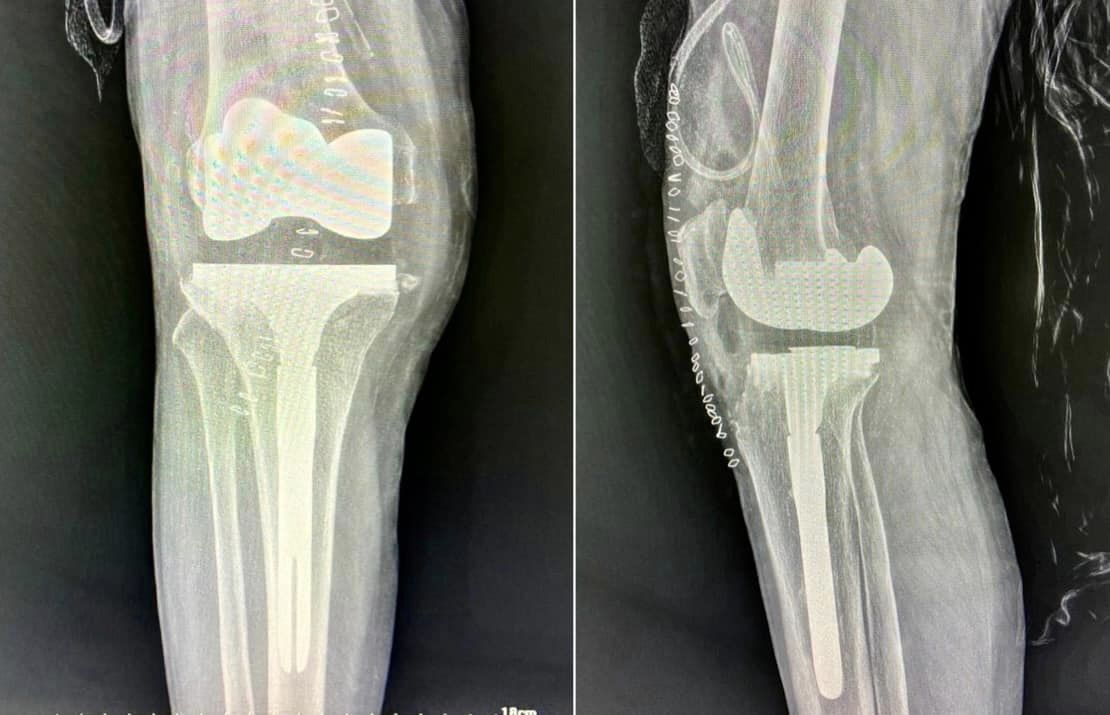

48-year-old male with windswept deformity of knees due to rheumatoid arthritis, both femoral lateral condyles are hypoplastic. Left tibia has a medial bone defect of 20 mm. Treated with long stem prostheses for tkr (total knee replacement) with semi-constrained liners. For the left knee bone defect, bone grafting was done with cc screw fixation.

In such extensively damaged knees it is important to keep all options in hand and pre-plan properly preferably on the computer to give optimum result.